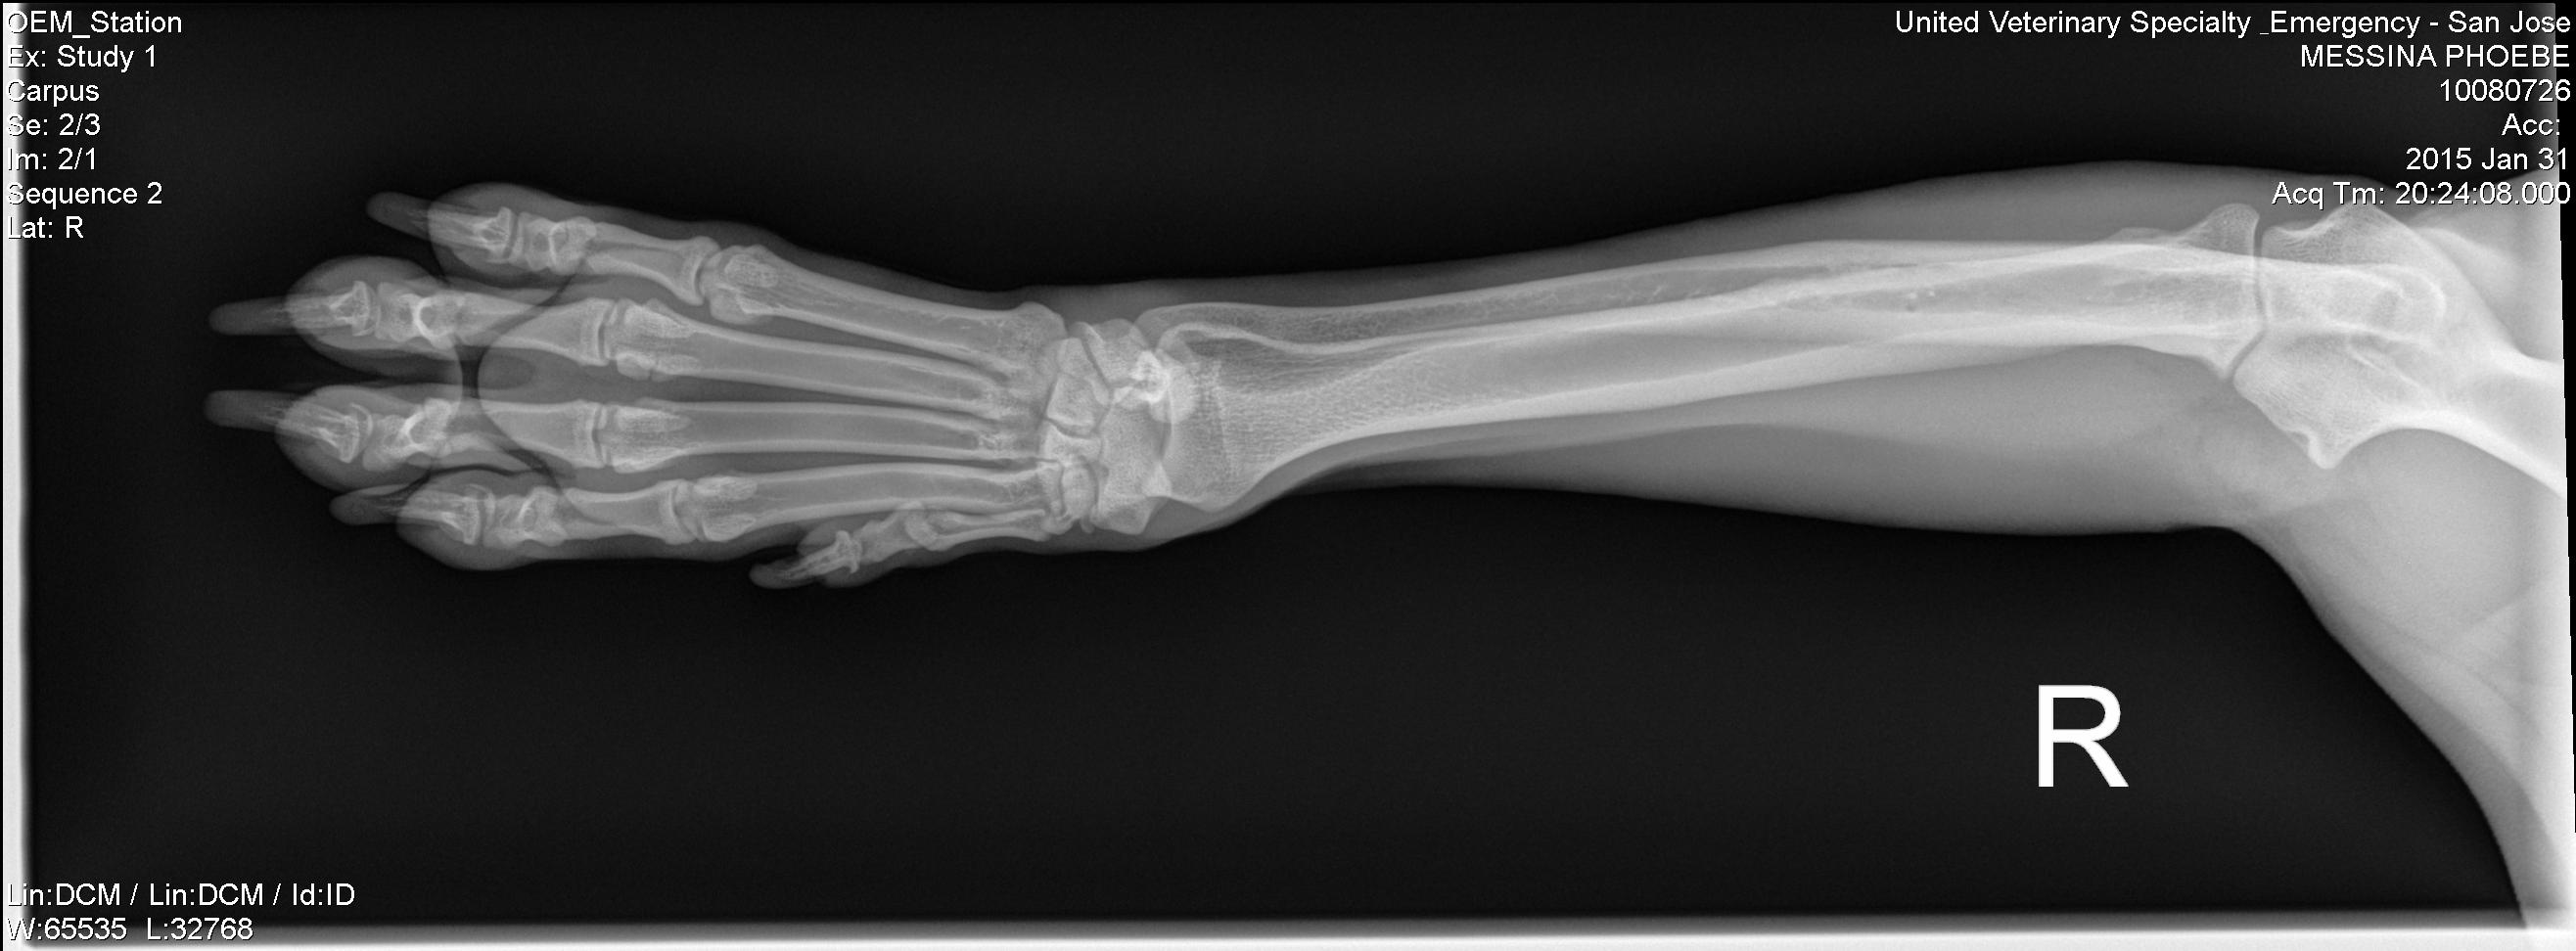

The x-rays revealed a fracture on her right “knuckle” bone. The official diagnosis:

“transverse fracture of axial sesamoid 4th metacarpophalyngeal joint with minimal displacement. The fracture is undisplaced so should heal quickly.”

Whew! that is a mouthful. In short, it is a simple fracture that should heal properly after wearing a splint for 3-4Β weeks.